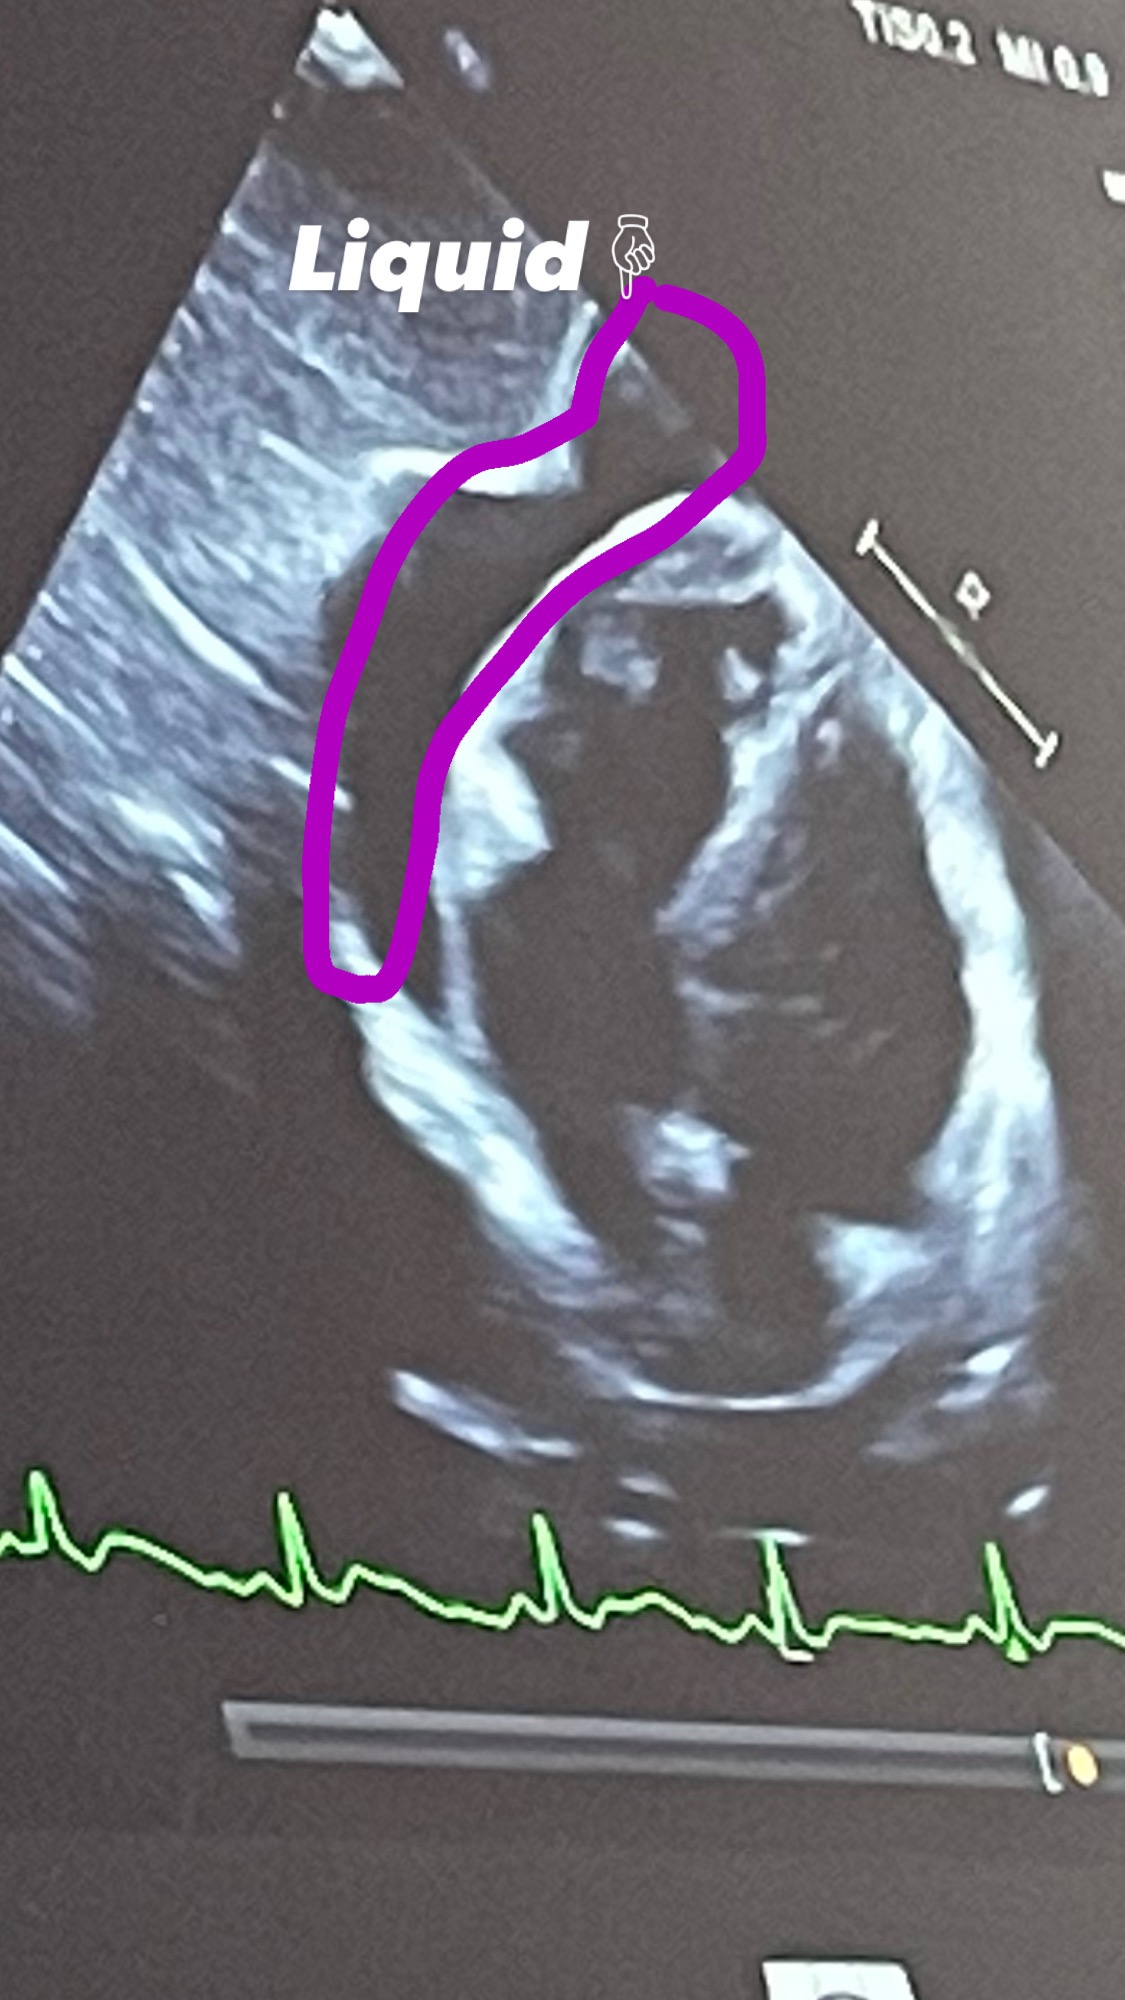

They did a de-bulking to see what it was and found it was a desmoid tumor (noncancerous) and wanted to start chemotherapy (IV), which made it horribly bigger and worse, wrapping around my spinal cord, ribs, and crushing my muscles. It was slowly entering my lungs, causing shortness of breath and liquid to reach near my heart.

They found the liquid in my chest, did surgery to drain it, and then ran more tests and found that I have Sarcoma. (Fuck cancer!)